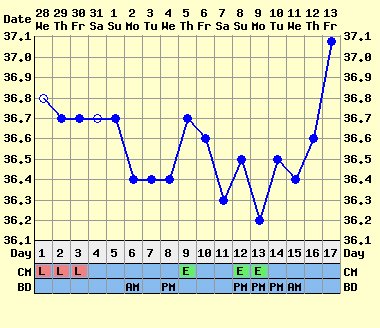

3 fázisúnak azt a görbét nevezik, amelyik úgy néz ki, mint a tied.

:D:D A ciklus első felében neked pl. 36,6 alatt van a hőd, pé. után felugrik 36,7-9, és aztán kezdődik egy újabb szakasz, amelyben még följebb áll be. Ezek igen gyakran babás görbék, mert a beágyazódás után észlelhető ez az újabb hőemelkedés.

De a görbéd így ránézésre is igen-igen biztató!!! Nagyon drukkolok!!!